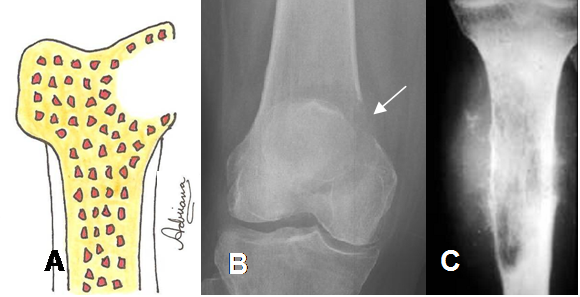

Fig 29. Lesión moteada.

A: Diagrama de lesión moteada, cuyos borde no son definidos.

B: Rx AP. Lesión de bordes mal definidos, en la cabeza femoral

C: RM coronal en T1. La lesión se extiende hasta la diáfisis del fémur, secundaria a osteosarcoma.